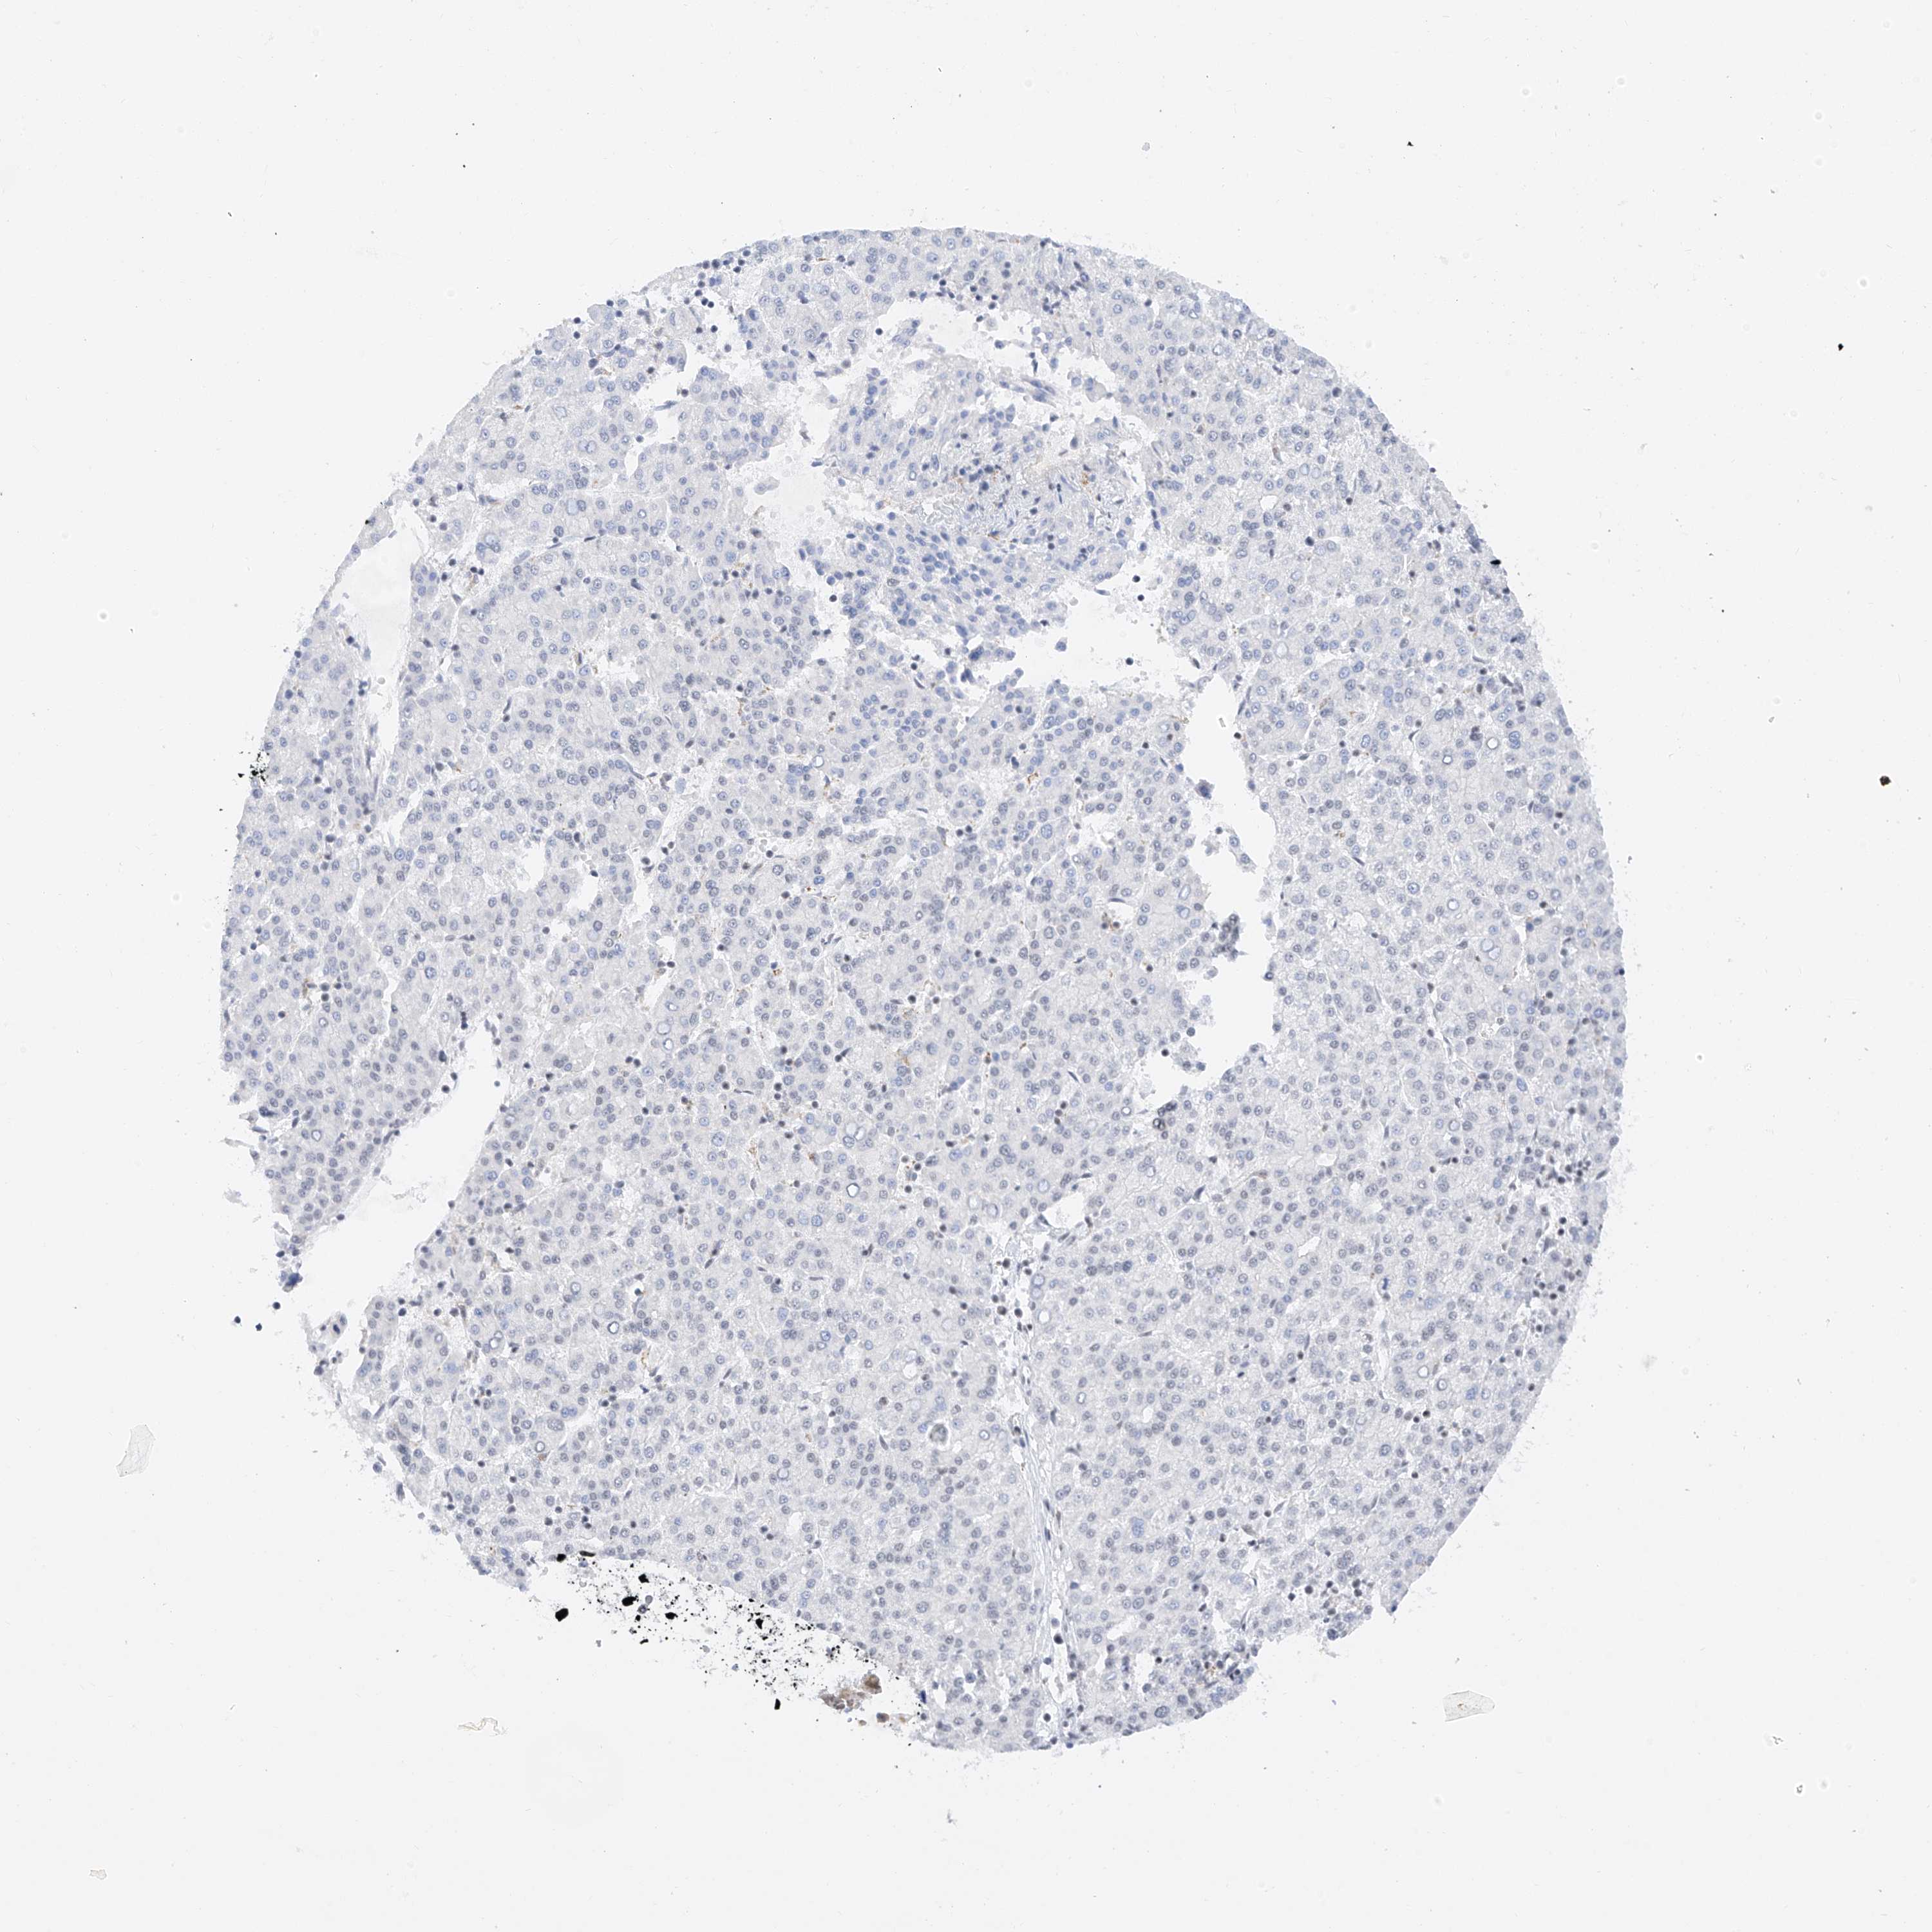

LIVER CANCER - Protein expressioni

A mouse-over function shows sample information and annotation data. Click on an image to view it in a full screen mode. Samples can be filtered based on level of antibody staining by selecting one or several of the following categories: high, medium, low and not detected. The assay and annotation is described here.

Note that samples used for immunohistochemistry by the Human Protein Atlas do not correspond to samples in the TCGA dataset.

Antibody stainingi

Antibody staining in the annotated cell types in the current human tissue is reported as not detected, low, medium, or high, based on conventional immunohistochemistry profiling in selected tissues. This score is based on the combination of the staining intensity and fraction of stained cells.

Each image is clickable and will lead to virtual microscopy that enables deeper exploration of all samples and also displays staining intensity scores, fraction scores and subcellular localization as well as patient and tissue information for each sample.

Antibody HPA029329

Staining

High

Medium

Low

Not detected

Intensity

Strong

Moderate

Weak

Negative

Quantity

>75%

75%-25%

<25%

None

Location

Nuclear

Cytoplasmic/membranous

Cytoplasmic/membranous,nuclear

Cholangiocarcinoma

Carcinoma, Hepatocellular, NOS